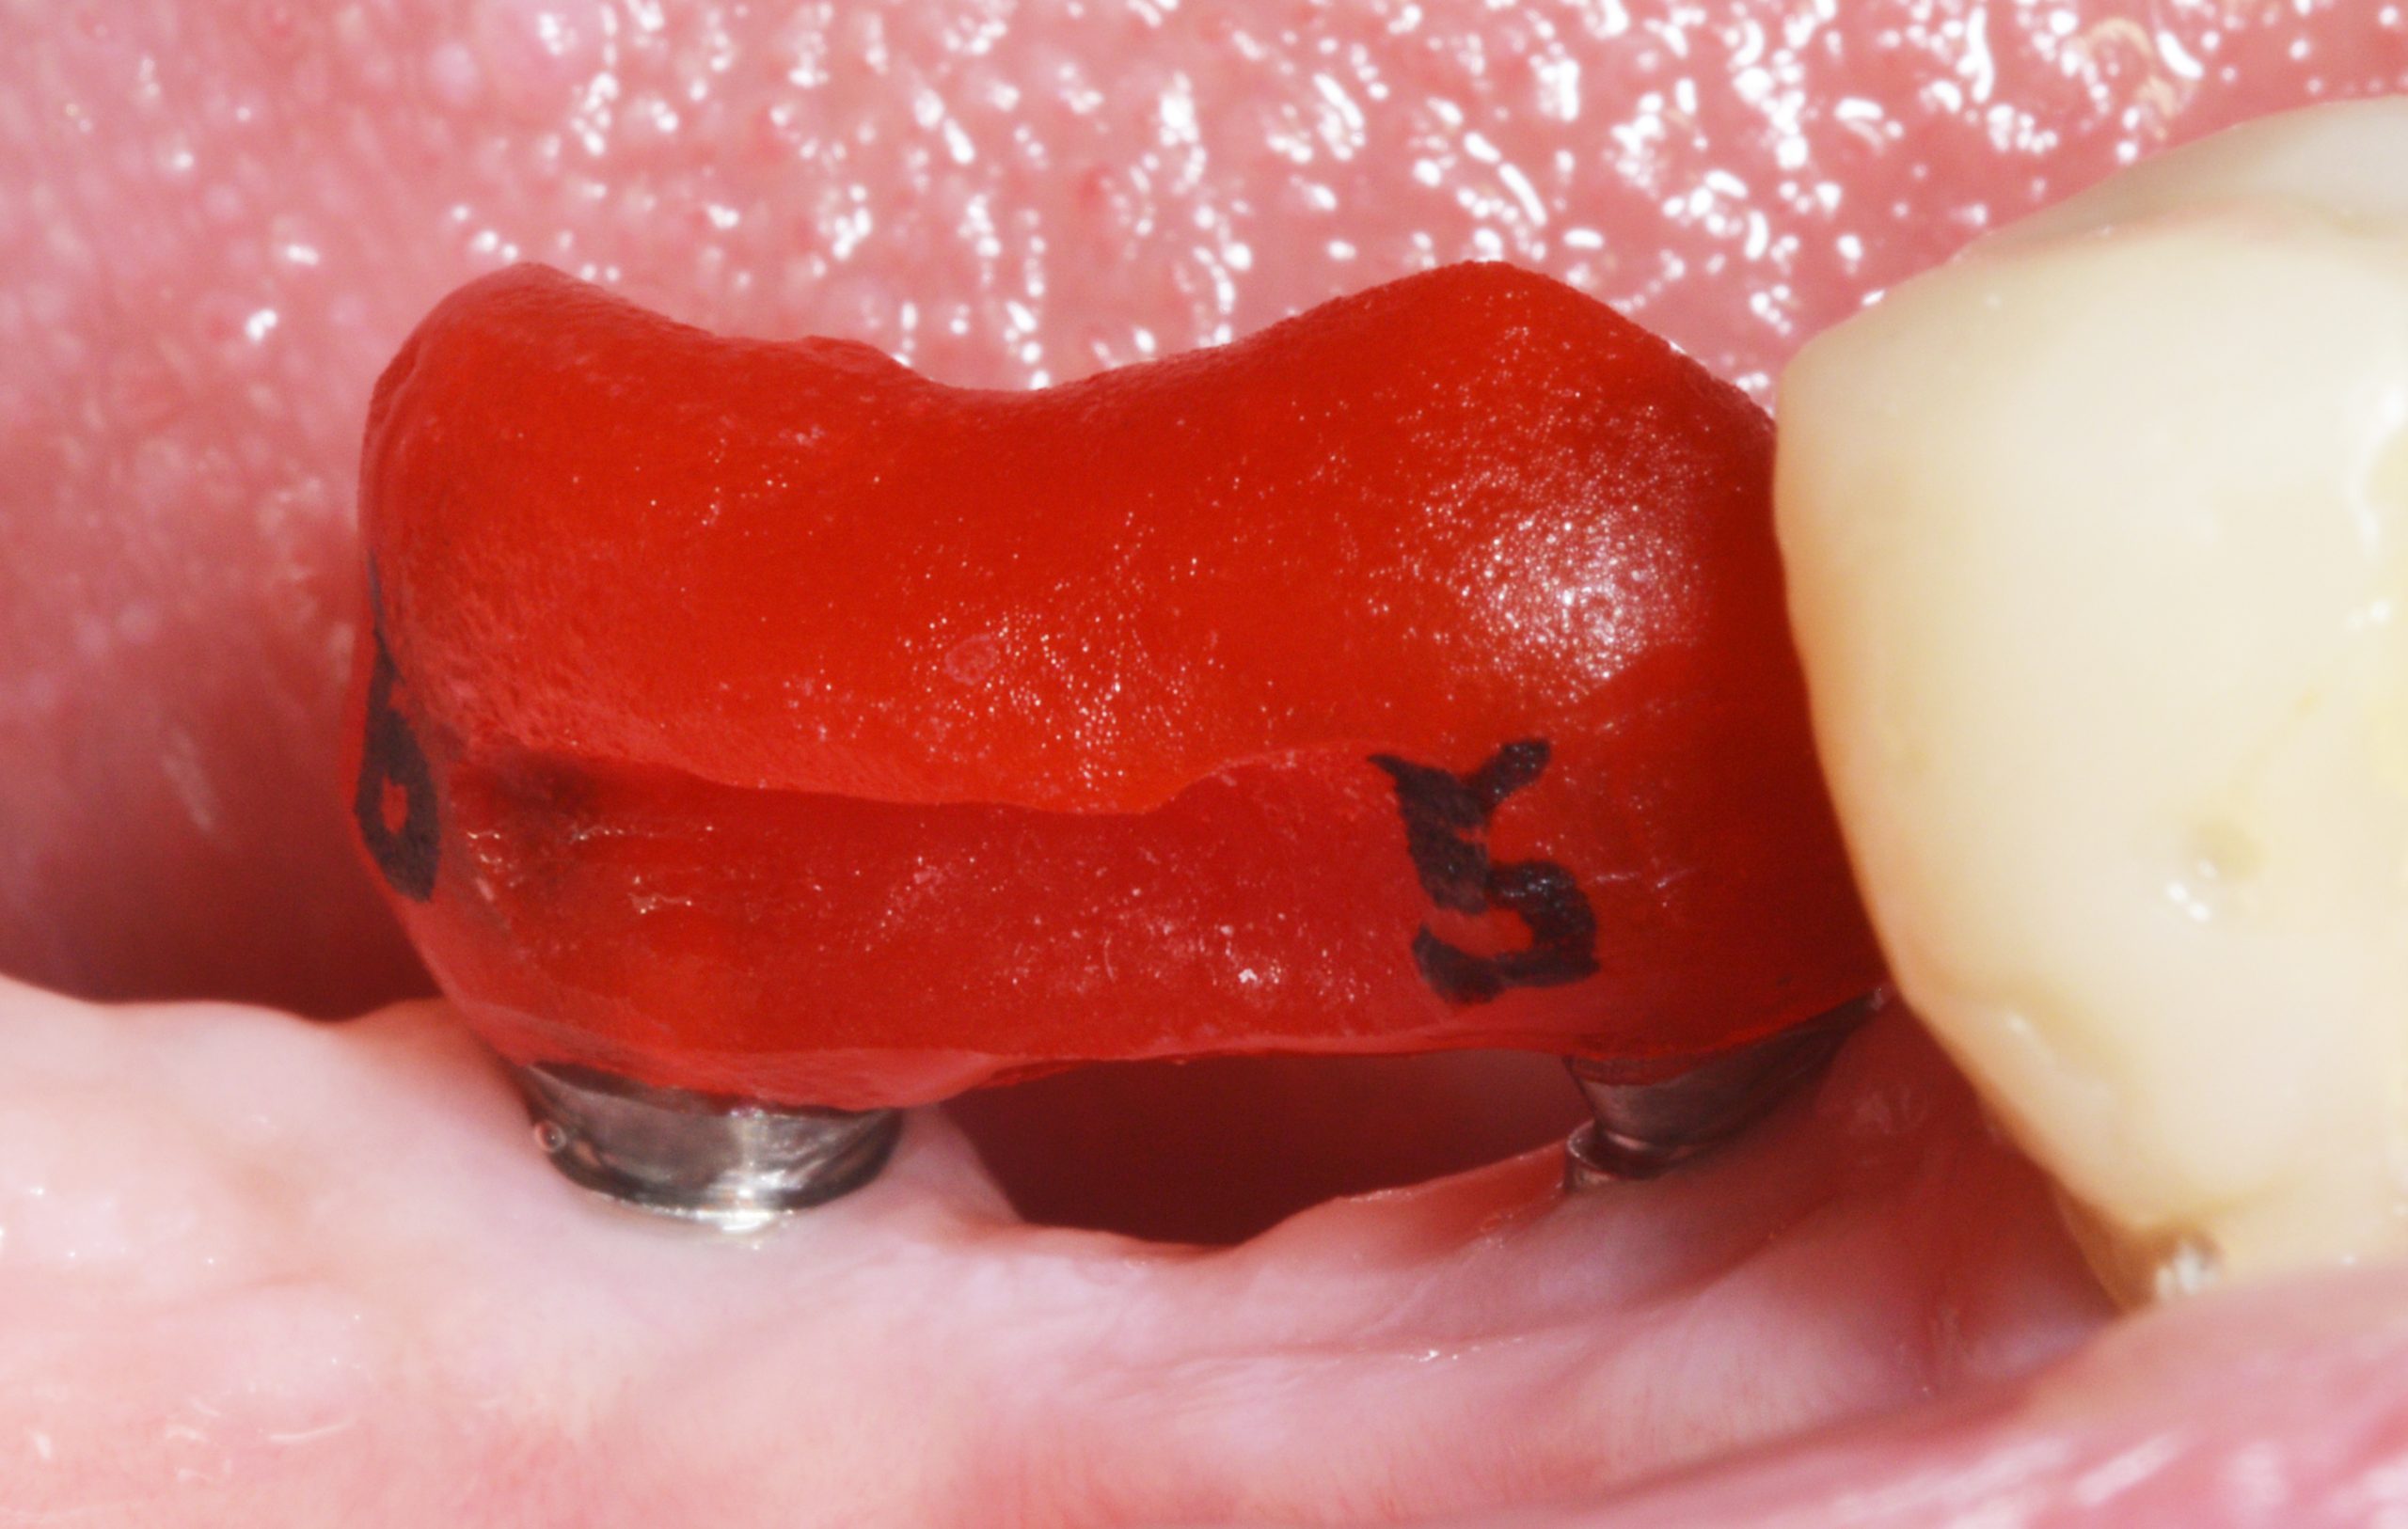

Im Zuge der Behandlung wurde auch die defekte Krone 44 neu gestaltet. Die Implantatpassung wurde wegen des nie auszuschließenden, sehr geringen Verzuges bei der Abformung sicherheitshalber mit einer Implantatkontrollschiene verifiziert.

Intraoral lässt sich die Schiene straff, aber spannungsfrei aufsetzen.